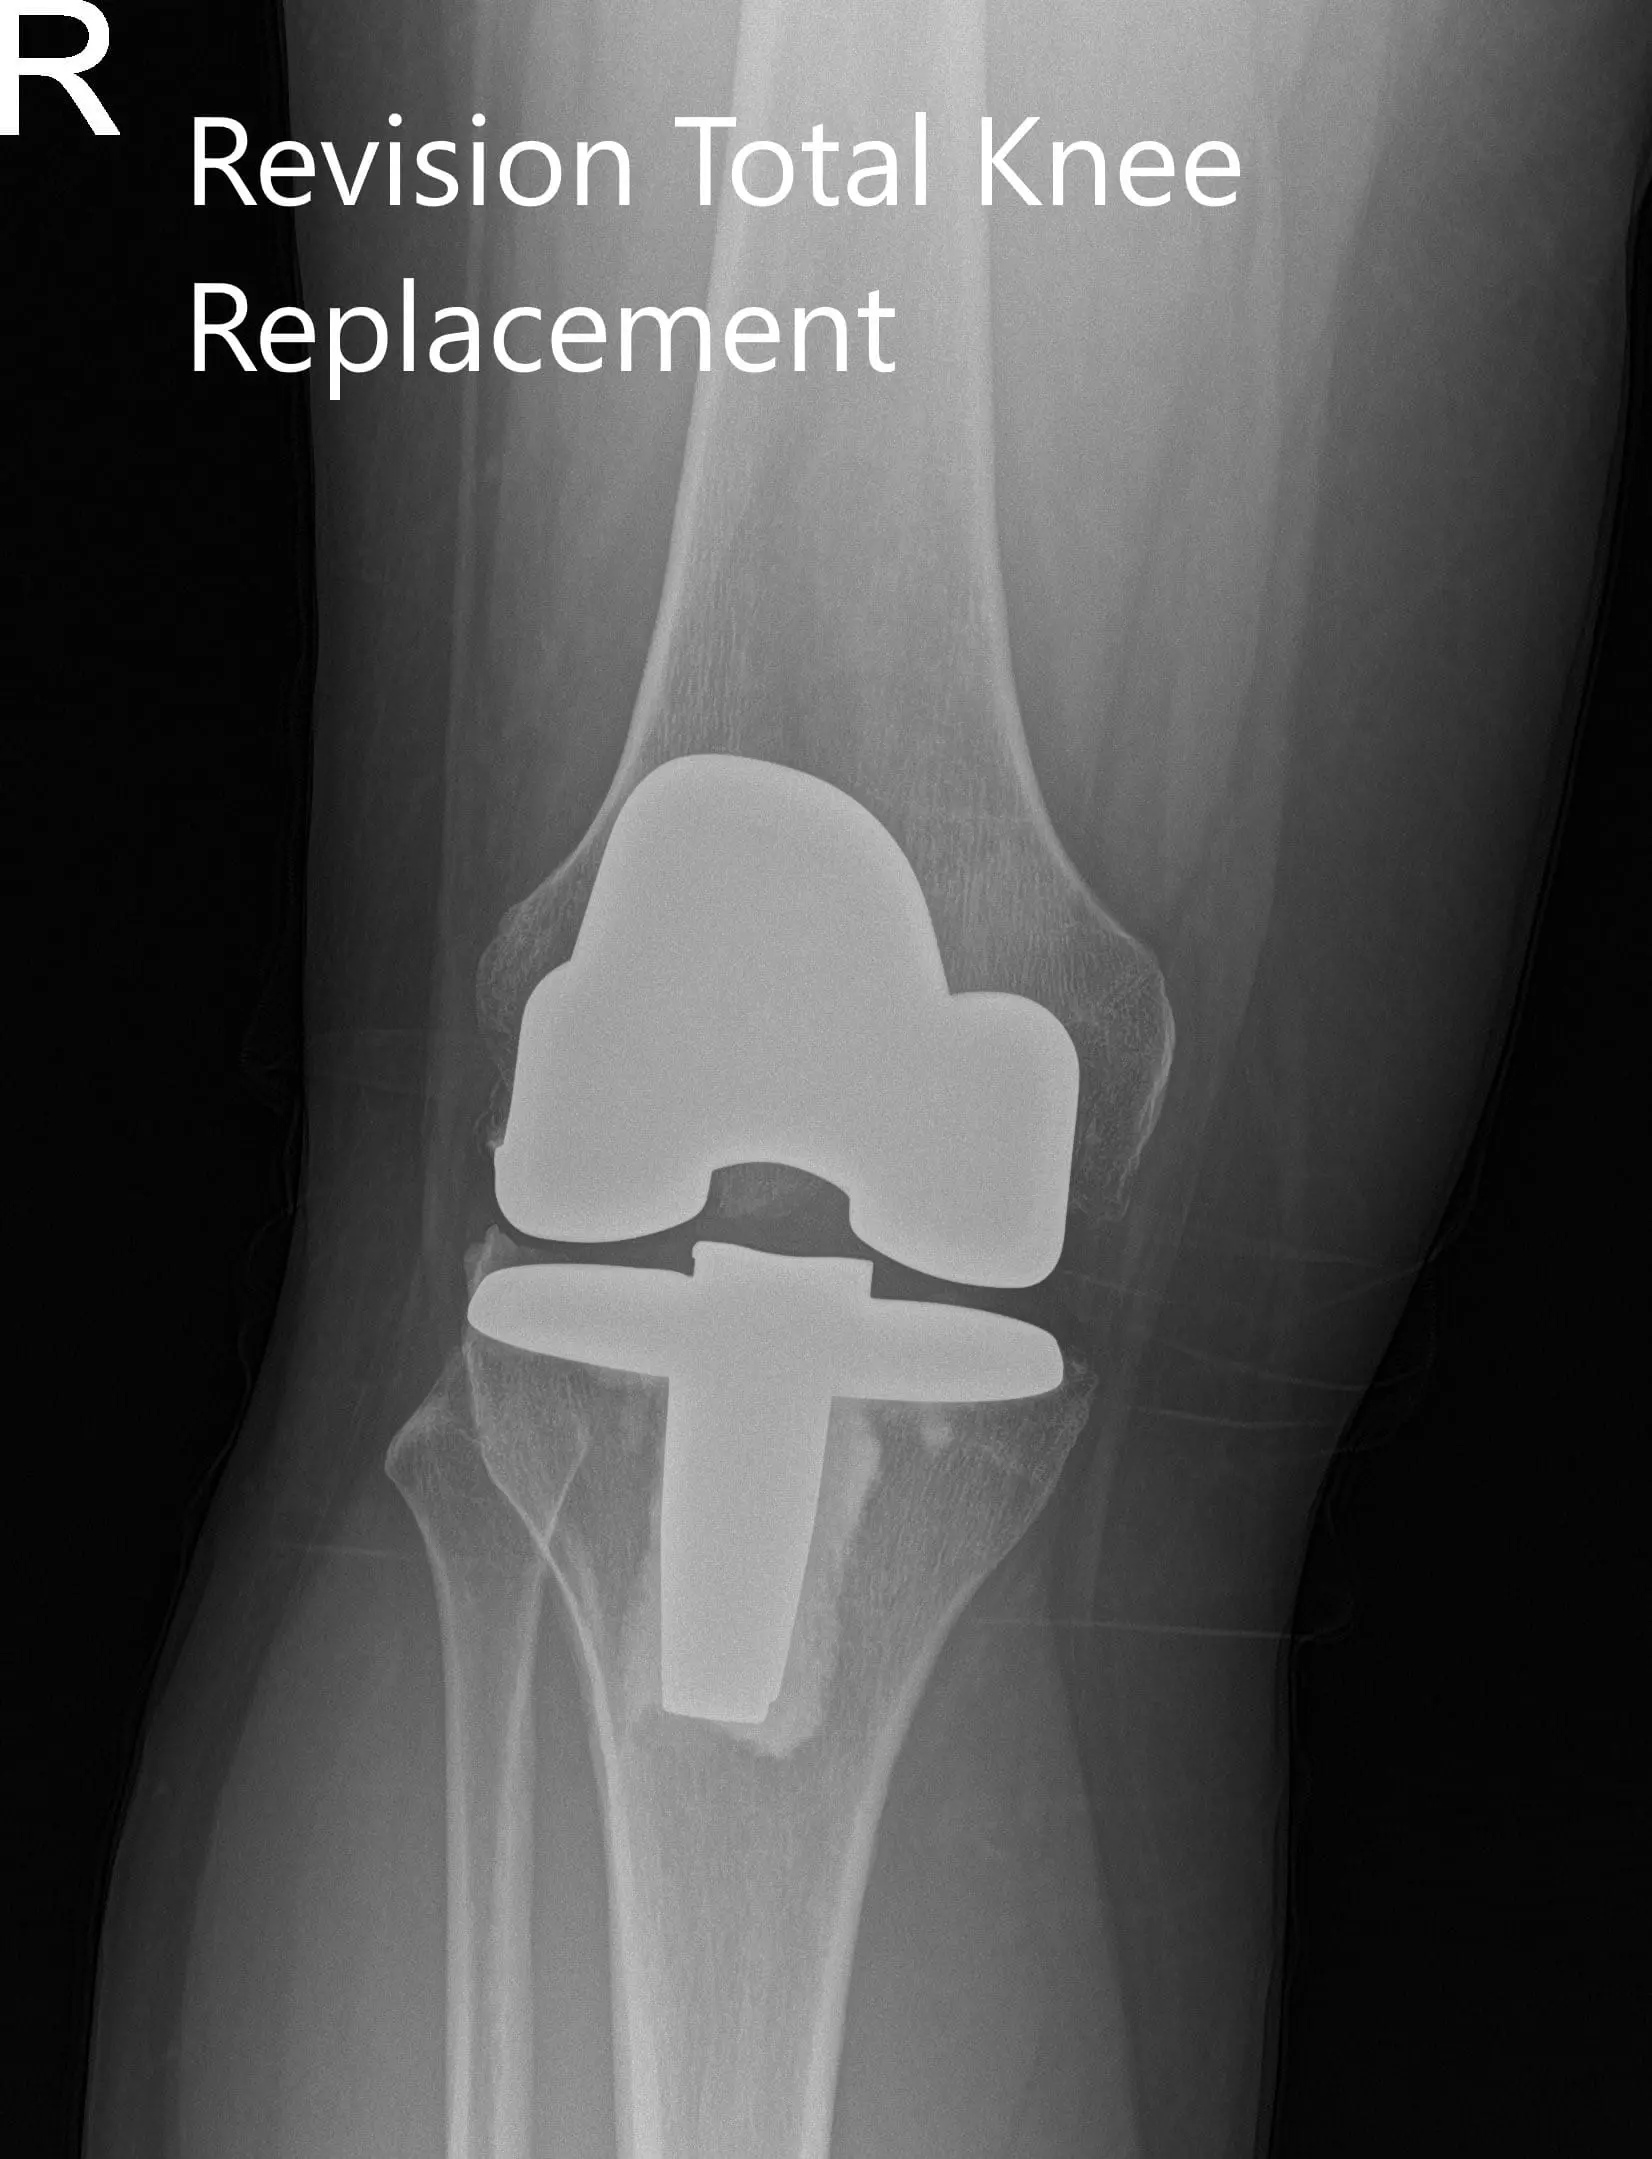

Preoperative x-ray showing the anteroposterior and lateral views of the right knee

PREOPERATIVE DIAGNOSIS(ES): Failed Right knee unicondylar knee replacement.

Postoperative x-ray showing the anteroposterior and lateral views of the right knee.